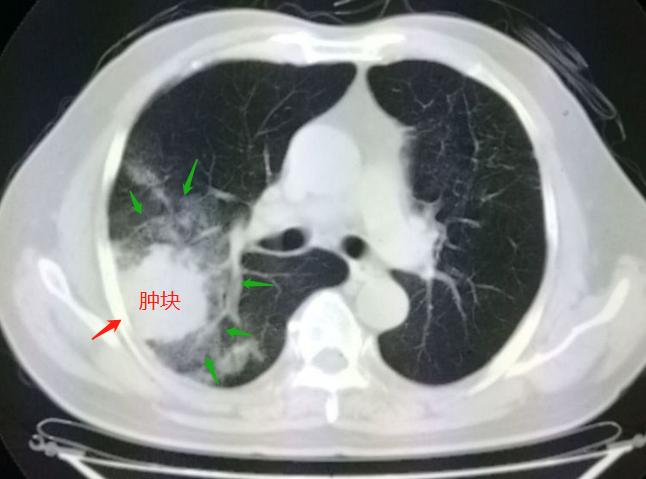

老人的右肺上长了一个3.5厘米的大肿块,不太规则,周围还有一大片云雾状的高密度影:

我们知道,长年抽烟的人,肺里发现大肿块,首先就要想到肺癌的可能(肺鳞癌和小细胞肺癌与*草烟**暴露关系密切)!需要深入分析影像特征,并且要结合化验检查。

从上图我们可以看到,在肿块的周围有一大片磨玻璃密度的影子,边缘是模糊不清的,这提示有炎症的存在(肺癌常常边界较清晰),然后我们等到了他的血液检测结果:肿瘤标志物正常,白细胞1.3万(正常值为4千到1万,升高常提示有感染)。